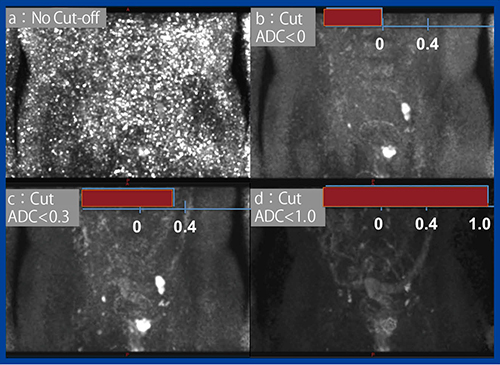

一方,Computed DWIでは骨に高輝度なノイズが出ると,それが骨転移に見えてしまうという問題がある。DWIはもともとSNRが低いため,ノイズがあると非常に多くのピクセルがb=0の信号よりも高信号となり,b値を上げることで高輝度になってしまう。この高輝度ノイズは各スライスに現れるため,Computed DWI をMIP処理すると画像全体に天の川のように顕著に分布し,内部が確認できなくなる(図2 a)。

実はこのとき,計算上はADCが負の値(ADC<0)となっており,数学的には明らかな誤りである。そのため,

ADC<0のピクセルをカットすることで,内部を確認可能となる(図2 b)。子宮内膜がんや神経膠腫のminimum ADC値に関する論文で,腫瘍の最小ADC値は0.4×10−3mm2/s以下にはならないことが報告されており2),ADC<0.4のピクセルをカットすれば,さらに背景信号が抑制された適切な画像が得られる(図2 c)。なお,試しにADC<1.0のピクセルをカットすると,当然腫瘍も消えてしまう(図2 d)。このように,Ziostation2のComputed DWIには,この非現実的低ADC値を任意値でカットするフィルタが搭載されている。

図2 Computed DWI